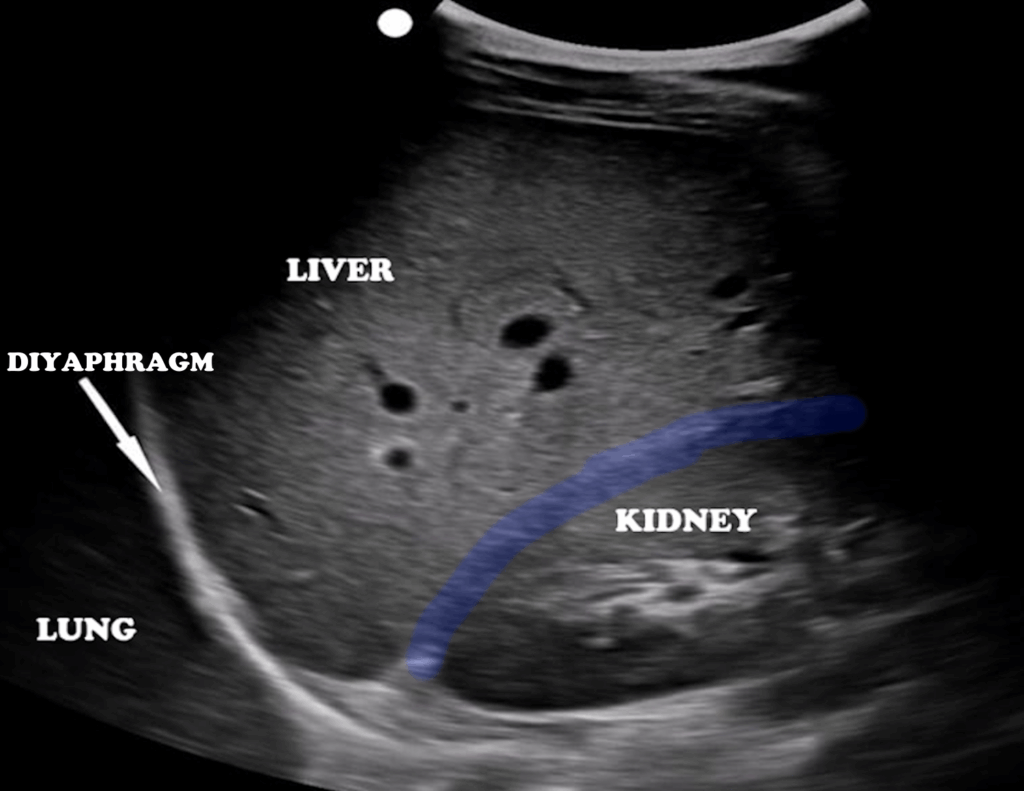

The hepatic parenchyma appears homogeneous and moderately echogenic (Figure 2).